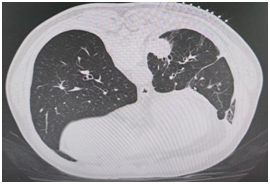

术后

患者(男性,60岁)因长期咳嗽、胸痛等症状入院,经CT检查、支气管镜及肺穿刺活检,确诊为肺腺癌。

在廖江荣的指导下,榕江县人民医院医生通过CT精准定位肿瘤位置,为患者实施CT引导下经皮肺穿刺微波消融术,使用微波消融针将微波能量直接作用于肿瘤组织,使肿瘤细胞凝固性坏死,整个手术仅短短30分钟便顺利完成。术后,患者未出现任何不良反应,恢复良好。